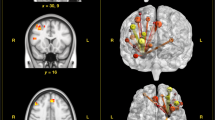

Then we set up a latent regression model to examine the associations between the three latent brain factors and our four geocoded land use variables, while controlling for age, sex and years of education. Geocoded land use variables were entered simultaneously as manifest predictor variables. Interestingly, the amount of forest within 1 km radius of the home address of the participants significantly predicted global amygdala integrity (β = 0.232, SE = 0.090, p = 0.010, Fig. 2). We obtained similar results when taking the amount of forest within a 500 m or 2 km radius into account (path between forest and amygdala 500 m: Wald χ2 (1) = 6.02, p = 0.014; 2 km: Wald χ2 (1) = 6.62, p = 0.010) but we decided to report the 1 km radius variable because it takes an average person 10–12 min to walk 1 km and therefore we would consider the area within 1 km around the house as the walking distance an older adult will very likely be able to cover.

Depiction of the structural equation model with urban land use with in the radius of 1,000 metres around the individuals’ households. Squares represent observed variables and circles represent latent variables. Single headed arrows represent directional effects (the numbers next to it are the standardized regression coefficients), the single headed arrows from latent factors to manifest variables are an exception and represent factor loadings, double headed arrows between latent or manifest variables represent covariances between the variables and double-headed arrows with both heads pointing on a manifest variable represent the variance of a variable. All means were fixed to zero as the data were z-standardized. We report standardized estimates for estimates with p < 0.05. We controlled for age, sex and years of education, however these arrows are not included to increase readability of the graph. Abbreviations: Amyg: amygdala, pACC: perigenual anterior cingulate cortex, DLPFC: dorsolateral prefrontal cortex, VBM: grey matter probability extracted from voxel-based morphometry conducted on T1 weighted images; MTR: magnetisation transfer ratio; MD = mean diffusivity extracted from diffusion weighted imaging. The brain images depicted are based on the colin27 brain atlas40 and created using MRIcron (http://people.cas.sc.edu/rorden/mricron/install.html).

Furthermore, a Wald test testing the present model against one where this path is equal to zero was significant (Wald χ2 (1) = 6.31, p = 0.012). All other paths between geocoded land use variables and brain factors were non-significant (β < 0.123, p > 0.084).